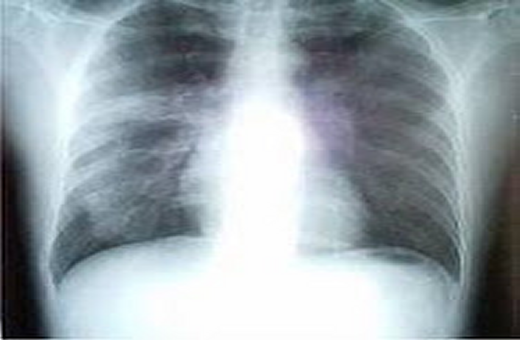

الأمراض الصدرية

الأمراض الصدرية دليلك الشامل ويب طب

الأمراض الصدرية الأسباب وطرق الوقاية

تخصص الداخلية الصدرية Pulmonology وكل ما تريد معرفته عنه Lookinmena

الأمراض التي تصيب الجهاز التنفسي الموسوعة المدرسية